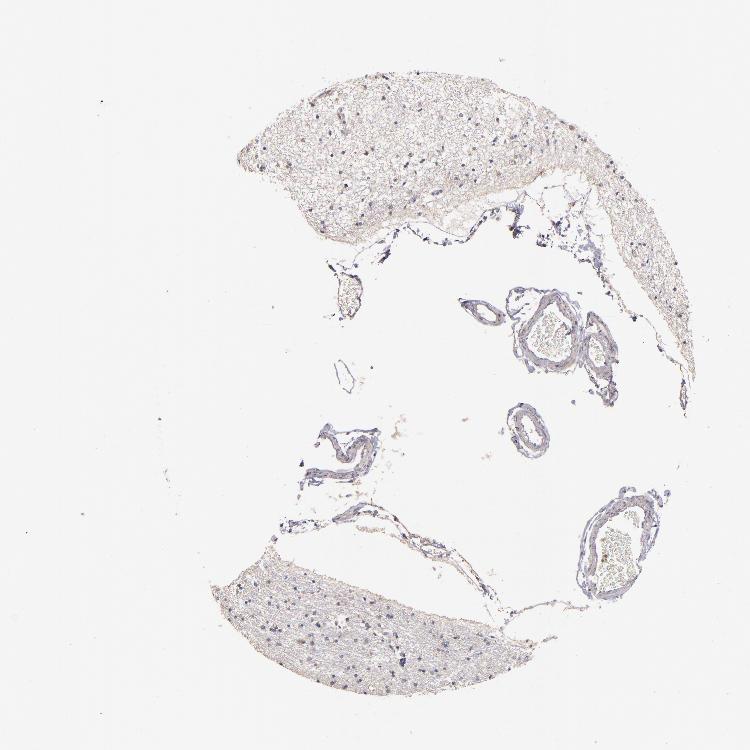

HIPPOCAMPUS - Antibody stainingi

Antibody staining in the annotated cell types in the current human tissue is reported as not detected, low, medium, or high, based on conventional immunohistochemistry profiling in selected tissues. This score is based on the combination of the staining intensity and fraction of stained cells.

Each image is clickable and will lead to virtual microscopy that enables deeper exploration of all samples and also displays staining intensity scores, fraction scores and subcellular localization as well as patient and tissue information for each sample.

Antibody HPA001825Antibody CAB003857

Glial cells Not detectedMedium

Neuronal cells Not detectedMedium